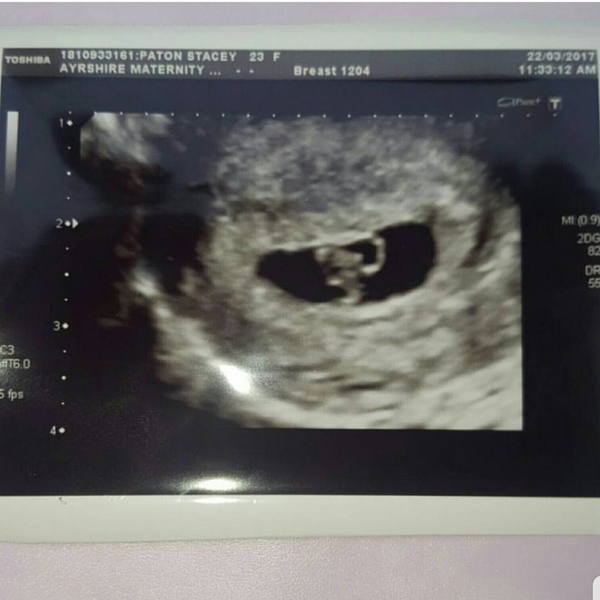

I had one at 8 weeks my last pregnancy (hot one booked for this bubba top on the 13th of Dec) you can see the baby and the heartbeat kinda looks like a sea horse here's a wee pic x

Late July Due Date